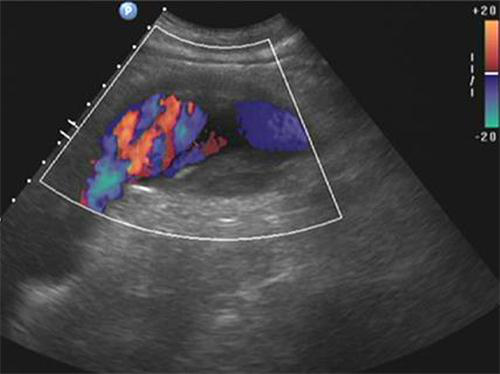

血流呈花色渦流,仔細(xì)掃查,為腹主動(dòng)脈的局部膨大,動(dòng)脈管壁完整,腔內(nèi)低回 聲考慮為血栓形成,超聲提示:真性動(dòng)脈瘤伴血栓形成。